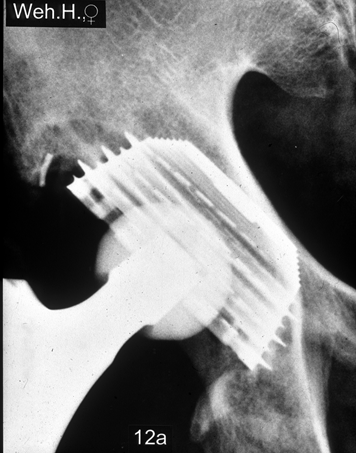

Abb. 12

unbeschichtet |

SLR Standard

SLR Lateral

|

HA-beschichtet |

Abb. 12a

SLR-Revisionsschaft